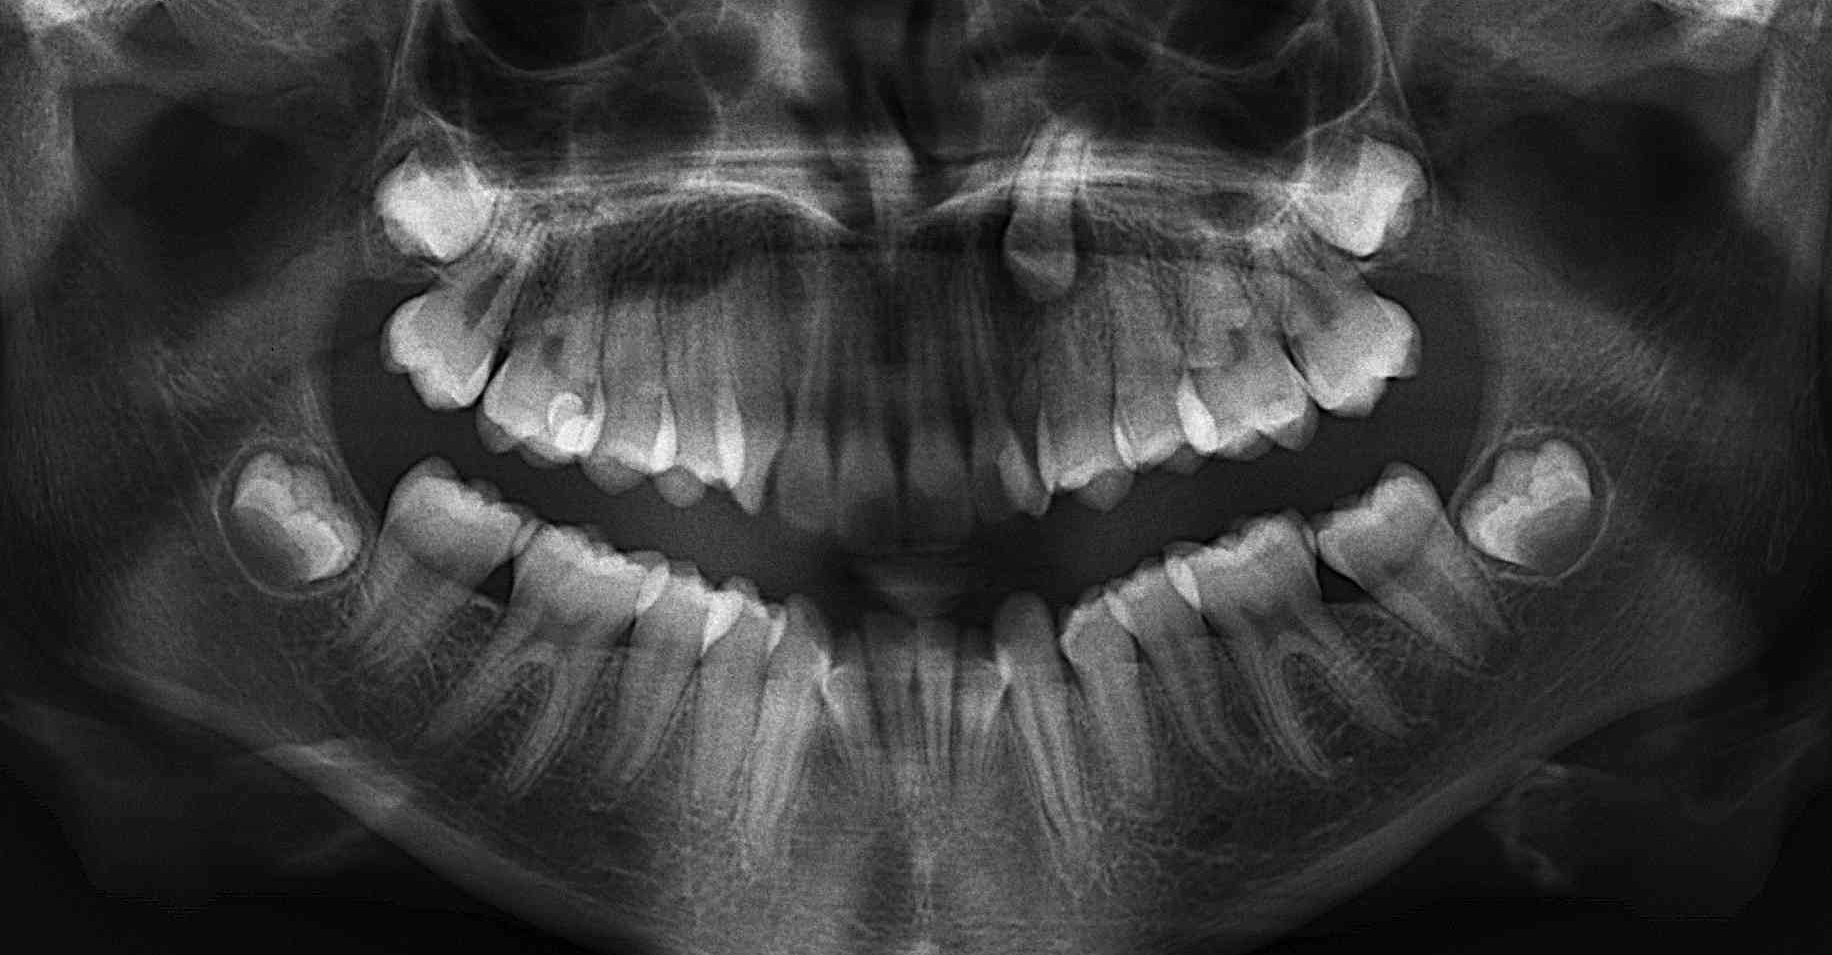

Le dépistage précoce est un élément fondamental de la réussite du traitement. Plus le patient est âgé et moins le potentiel d’éruption de la canine sera important. Une radiographie panoramique peut être réalisée de façon précoce pour permettre de diagnostiquer cette pathologie de l’éruption. Le praticien cherchera des dents manquantes, des dents surnuméraires, des problèmes concernant l’espace disponible sur l’arcade et orientera si nécessaire le patient vers un orthodontiste.